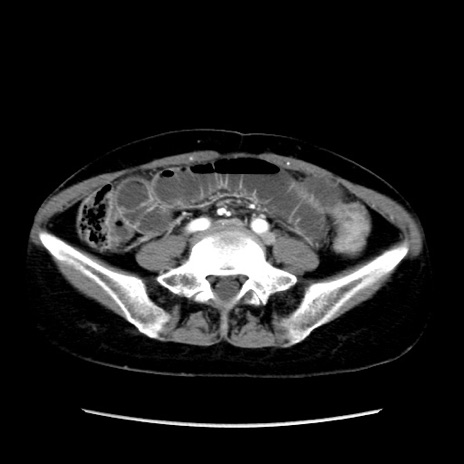

症例32(横断像)

【症例】40歳代 女性

【主訴】上腹部痛、嘔気・嘔吐

【現病歴】約9時間前頃から急に上腹部痛、嘔気、嘔吐が出現。改善しないため救急要請。

【既往歴】子宮頚癌(広汎子宮全摘術、放射線療法)、腸閉塞

【身体所見】腹部:平坦、軟、腸雑音亢進、上腹部を中心に腹部全体に圧痛あり。

【データ】WBC 8400、CRP 0.03